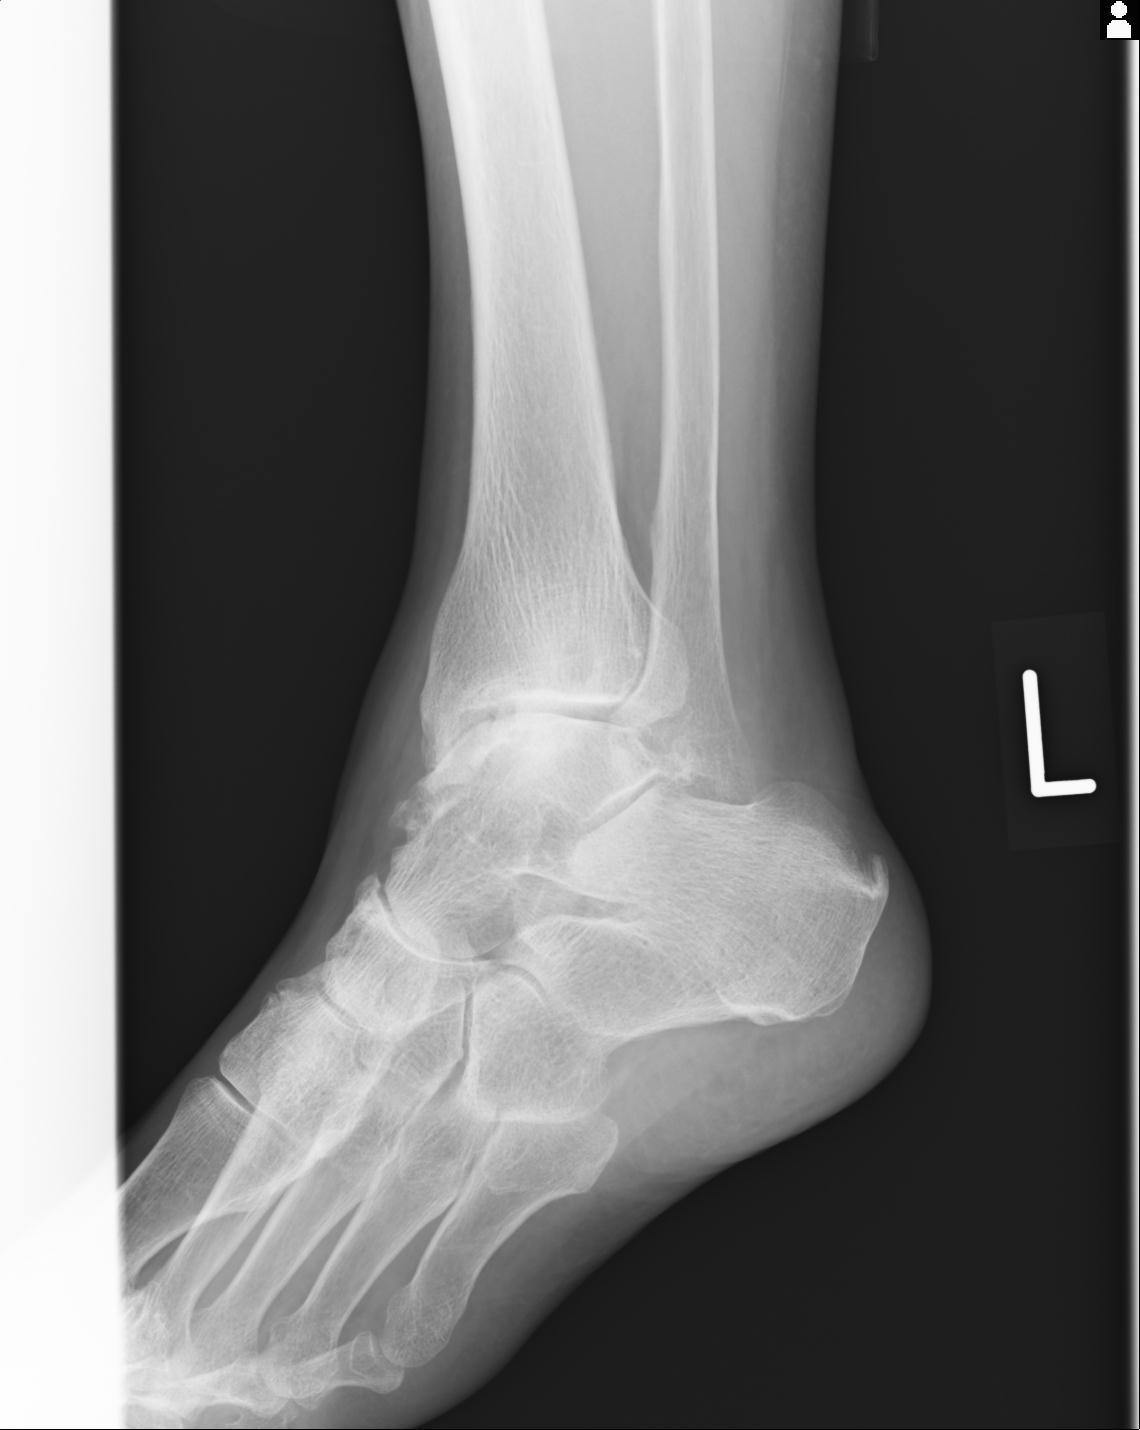

56476 8/28 4R 1/21 2R 左足関節 デジカメ写真 72歳女性 右足関節AS